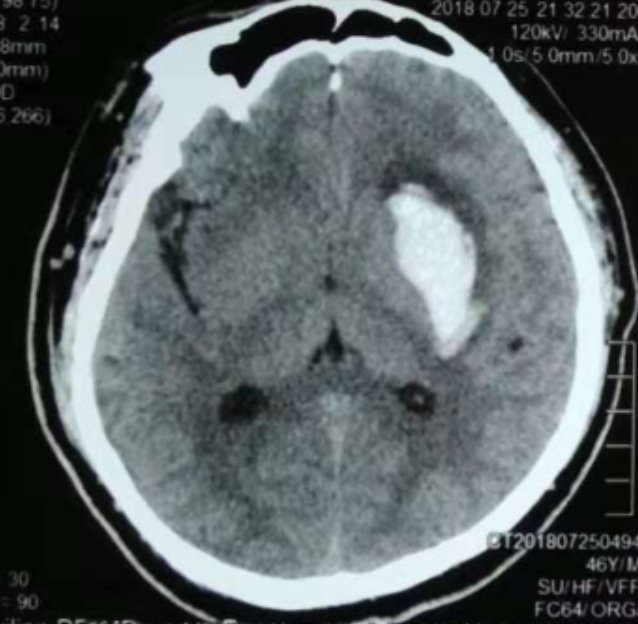

3個月前CT:腦出血